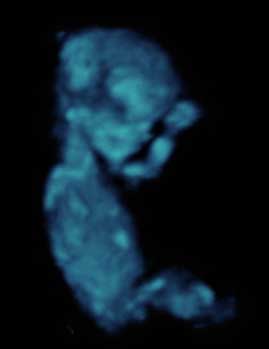

En la semana 11 de gestación, el feto mide alrededor de 4 cm desde la cabeza al coxis. La cabeza representa la mitad de su longitud, como se aprecia en esta silueta de perfil de una ecografía en 2D.

Silueta de un feto de 11 semanas

Mediante una herramienta de recorte, hemos podido aislar al feto al eliminar de la imagen la parte correspondiente al útero y a la placenta.